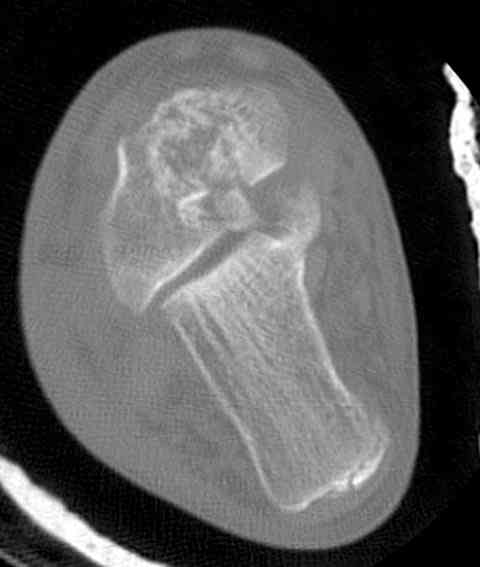

На ренгенограмме не уловил многоскольчатость тарана, чтобы доказать, конечно, можно было исследовать на КТ, потом КТ дает ориентацию фрагментов.

Два фрагмента суставной поверхности тарана можно восстановить боковой компрессией шурупами и дополнительно костная пластика.

(кстати, на нашем случае была применена костная пластика-allograft crouton для заполнения дефектов)